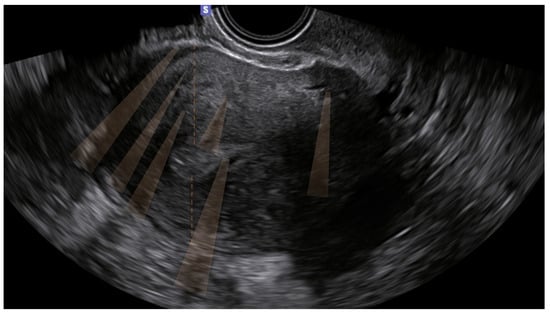

The 10 remaining patients (16%) presented only indirect signs, and the diagnosis was uncertain. Of these, none had junctional zone anomalies (Table 3) (Figure 1).

Figure 1. Ultrasound image of the uterus of one of the ten patients who presented only indirect signs (shadowing, highlighted in orange in the figure). The patient was symptomatic (dysmenorrhea).